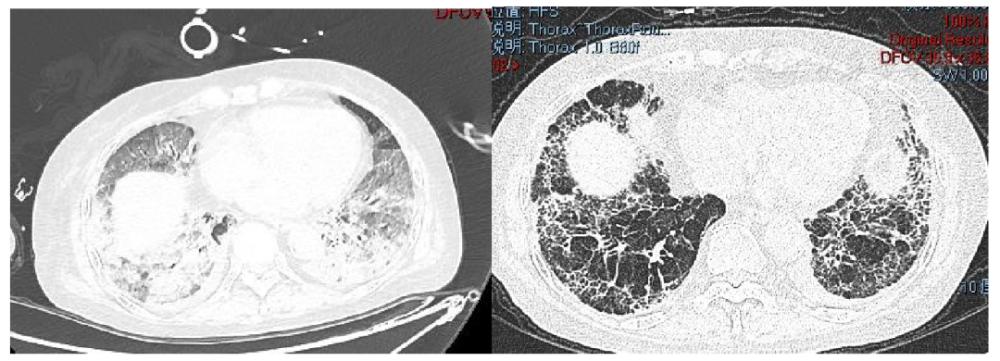

肺纖維化高發(fā)

《Nature Medicine》2021年發(fā)表了“Post-acute COVID-19 syndrome”,研究指出呼吸困難在60-100天的隨訪(fǎng)期內的發(fā)生率為42%-66%,有6.6%的患者因持續低氧血癥需要補充氧氣?;颊叱鲈汉?個(gè)月評估發(fā)現約25%的輕度至中度病例存在纖維化,在重癥病例居多的隊列中,約65%的康復者存在肺纖維化。

北京佑安醫院招募的7例新冠病毒肺炎患者(2例輕癥、4例重癥、1例危重癥)接受單次靜脈間充質(zhì)干細胞治療,結果顯示,移植14天內,間充質(zhì)干細胞治療顯著(zhù)改善了7例患者的肺功能,并且沒(méi)有明顯的不良反應。值得一提的是,在間充質(zhì)干細胞治療后2天內,所有患者肺功能和癥狀明顯改善,治療后2-4天內,所有患者全部癥狀包括:高熱、虛弱、呼吸短促、血氧飽和度低均消失,靜息血氧飽和度≥95%。2例輕癥患者和1例重癥患者在治療后10天內痊愈出院。